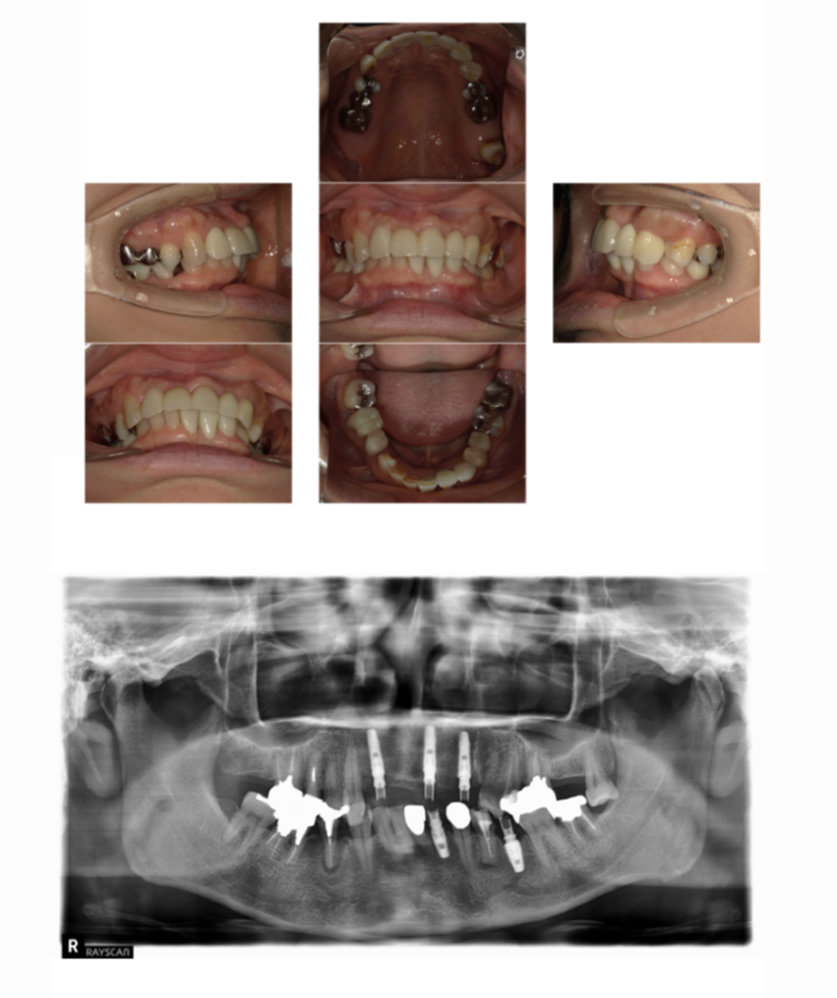

02 症例

歯の根の状態が悪いためインプラントにしたい

Before

After

| 治療内容 | 前歯の見た目が悪く、歯の根の状態も悪いのでインプラントにしたい。 |

| 患者様 | 50代女性 |

| 主訴 | 歯の根の状態が悪いためインプラントにしたい |

| 治療期間(目安) | 5ヶ月 |

| 治療費(税込:目安) | ¥2,702,700 (土台:5本、被せ物:7本) |

| リスク | 術後に多少の痛みや腫れが出ることがある。歯肉退縮がおきると、歯と歯肉の間に隙間が生じることがあります。 |